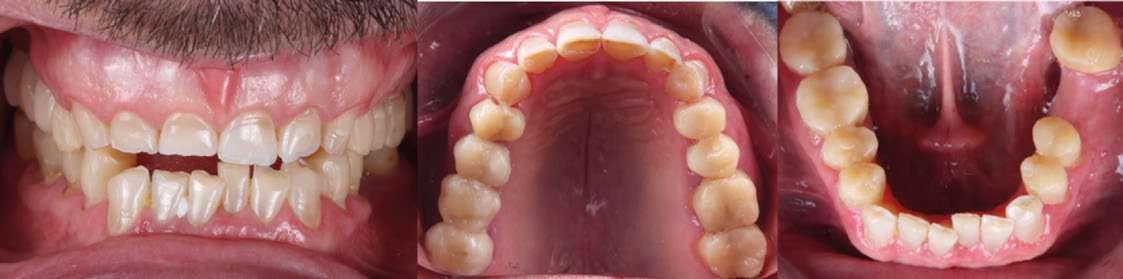

Presentación del caso

Paciente varón de 51 años que acudió a la Clínica Universitaria Odontológica (CUO) de la Universitat Internacional de Catalunya motivado por la necesidad de mejorar tanto su salud bucal como la estética de su sonrisa. El paciente manifestaba sensibilidad dental frecuente, especialmente al frío, episodios de incomodidad funcional durante la masticación y una marcada disconformidad con la apariencia estética de sus dientes. Entre sus principales expectativas destacó el deseo de obtener una rehabilitación integral que le proporcionara confort funcional y un resultado estético natural, siempre evitando procedimientos quirúrgicos o tratamientos excesivamente invasivos.

En la exploración clínica inicial se observaron signos compatibles con desgaste dental generalizado, pérdida de estructura dentaria a nivel incisal y oclusal, y presencia de restauraciones previas con

distintos grados de desajuste marginal. Se evidenció también una leve recesión gingival localizada y alteraciones en la alineación dentaria que afectaban a la estética de la sonrisa. El estado periodontal general era aceptable, con índices de placa y sangrado controlados, sin presencia de movilidad dentaria significativa.

Hallazgos clínicos iniciales

 Desgaste dental generalizado, compatible con erosión en palatinos de sector anterior superior y caras oclusales posteriores.

 Atrición en bordes incisales superiores e inferiores.

 Lesiones cervicales no cariosas (abrasiones por cepillado y abfracciones por sobrecarga oclusal).

 Presencia de puente metal-cerámica 1.5–1.7, con ausencia de piezas 1.6 y 3.6.

 Apiñamiento dental en incisivos inferiores y retroinclinación de incisivos superiores (torque negativo), diagnosticándose Clase II subdivisión 2.

Análisis estético

 Dientes cortos.

 Desgaste incisal irregular.

 Sonrisa alta con exposición gingival excesiva (“gummy smile”).

 Desbalance entre estética rosa y estética blanca.

 Canting anterosuperior.

Se recopilaron registros clínicos como fotografías extraorales e intraorales (Fig. 1–6) y digitales completos, incluyendo escaneados intraorales y registros de movimientos mandibulares. Los datos se integraron en un articulador virtual mediante el software de diseño digital (Exocad), montando los modelos maxilares, archivo de movimientos mandibulares y horquilla en formato STL.

Figura 1-3. Secuencia fotográfica extraoral inicial.

Figura 4-6. Análisis de la sonrisa del paciente.